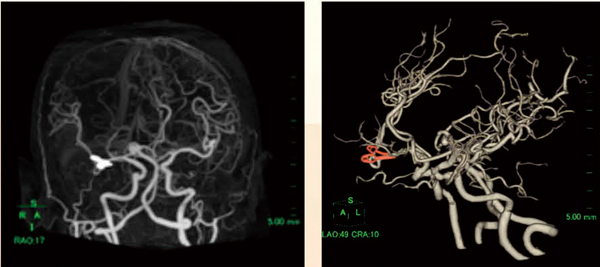

異なる撮影日の造影,非造影データをサブトラクションし,血管を抽出できるという従来のメリットに加え,今回,新たに脳実質や石灰化等の抽出を詳細に調節することが可能となった(図3)。また “位置合わせ”から“血管抽出”までのすべての作業を,画像を読み込むだけで全自動で行うことが可能である。

図3 クリップを残したサブトラクション画像